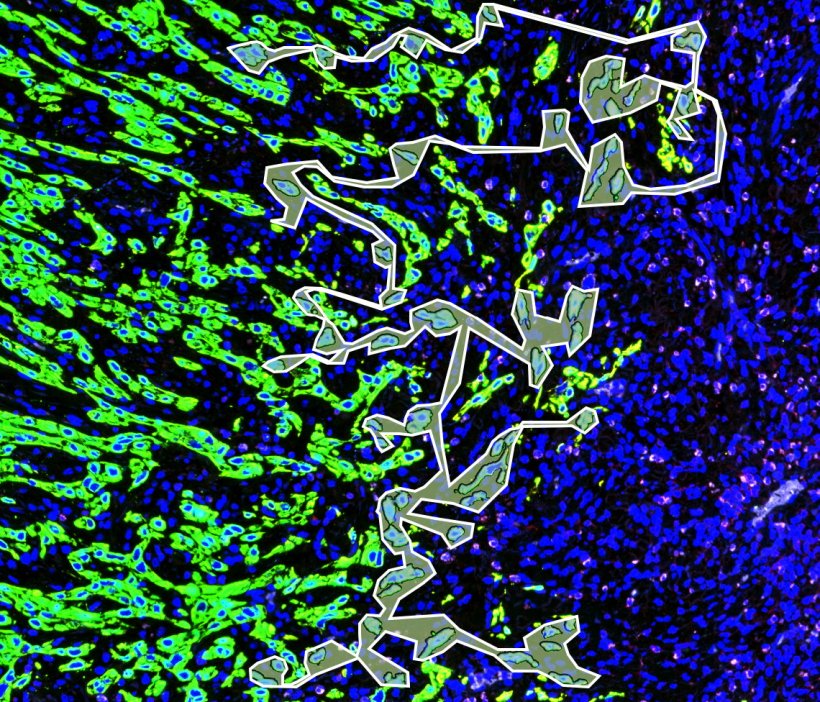

Bildquelle: Universitätsklinikum Heidelberg / Prof. Budczies

Sogenannte Tumorknospen sind Zellverbände von bis zu vier Zellen, die sich vom restlichen Tumorgewebe bei Karzinomen des Kopf-Hals-Bereichs ablösen. Ihr Vorhandensein ist Anzeichen für einen ungünstigen Verlauf der Erkrankung. Wie genau diese Tumorzellen „ticken“ haben Forschungsteams der Medizinischen Fakultät Heidelberg der Universität Heidelberg und der Technischen Universität München erstmals mithilfe einer räumlichen Analyse der genetischen Aktivität, der sogenannten Transkriptomanalyse, genauer unter die Lupe genommen. Sie untersuchten mit speziellen Techniken an Gewebeschnitten von Kopf-Hals-Tumoren und mit besonderem Fokus auf den Tumorknospen, wo welche Gene aktiv waren. Dabei entdeckten sie eine charakteristische Signatur von 28 Genen, in deren Aktivität sich die Knospen vom umliegenden Tumorgewebe und gesundem Gewebe unterschieden. Diese charakteristische Genaktivität gibt erstmals Hinweise auf die speziellen Eigenschaften dieser Krebszellen und deckte zudem Angriffspunkte für bestehende therapeutische Wirkstoffe auf.

„Die Schwierigkeit einer molekularen Charakterisierung dieser Tumorknospen liegt darin, dass Kopf-Hals-Tumoren insgesamt aus einer Vielzahl molekular sehr heterogener Zellen bestehen. Bisher war es nicht möglich, aus diesem Chaos das molekulare Profil der Tumorknospen herauszufiltern“, beschreibt Prof. Budczies. In dem von der Deutschen Krebshilfe geförderten und in Kooperation mit Kolleginnen und Kollegen der TU München durchgeführten Projekt griff das Team auf eine neue Methode der räumlich aufgelösten Transkriptom-Analyse zurück: Mit dieser Technik werden in markierten Arealen eines Gewebeschnitts sämtliche Moleküle der sogenannten Boten-RNA erfasst. Dabei handelt es sich um kurze Kopien von Abschnitten der Erbinformation im Zellkern, die Informationen zur Herstellung benötigter Proteine kodieren. Sie spiegeln die molekularen Prozesse wider, die in den Zellen zum Zeitpunkt der Entnahme abliefen, und geben Aufschluss über die Eigenschaften der Tumorzellen. Die Forschenden markierten an digitalisierten Gewebeschnitten aus HPV-negativen Tumoren zum einen die Tumorknospen und zum anderen den Haupttumor, von dem sich diese ablösen. „Die verwendete Technik erlaubte es, die RNA präzise aus den ausgewählten Tumorarealen zu analysieren und so erstmals die verschiedenen Zelltypen anhand des Transkriptoms zu unterschieden“ sagt Iordanis Ourailidis, Doktorand und Erstautor des Artikels.